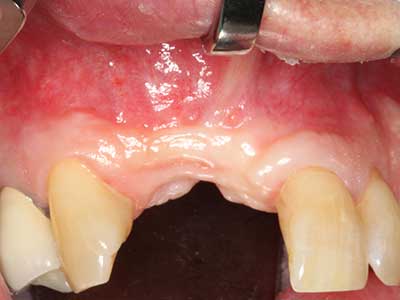

Fig. 12: After six months of healing, the alveolar ridge is vital and sufficiently dimensioned in all planes.

Fig. 16: The intraoral conditions are also stable with embedding of the implants in keratinized gingiva.